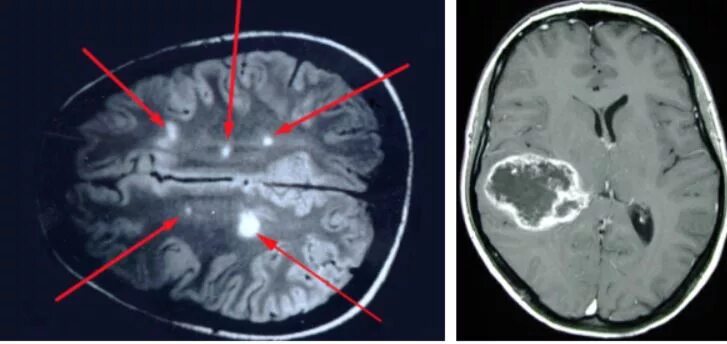

Как выглядит опухоль на снимках